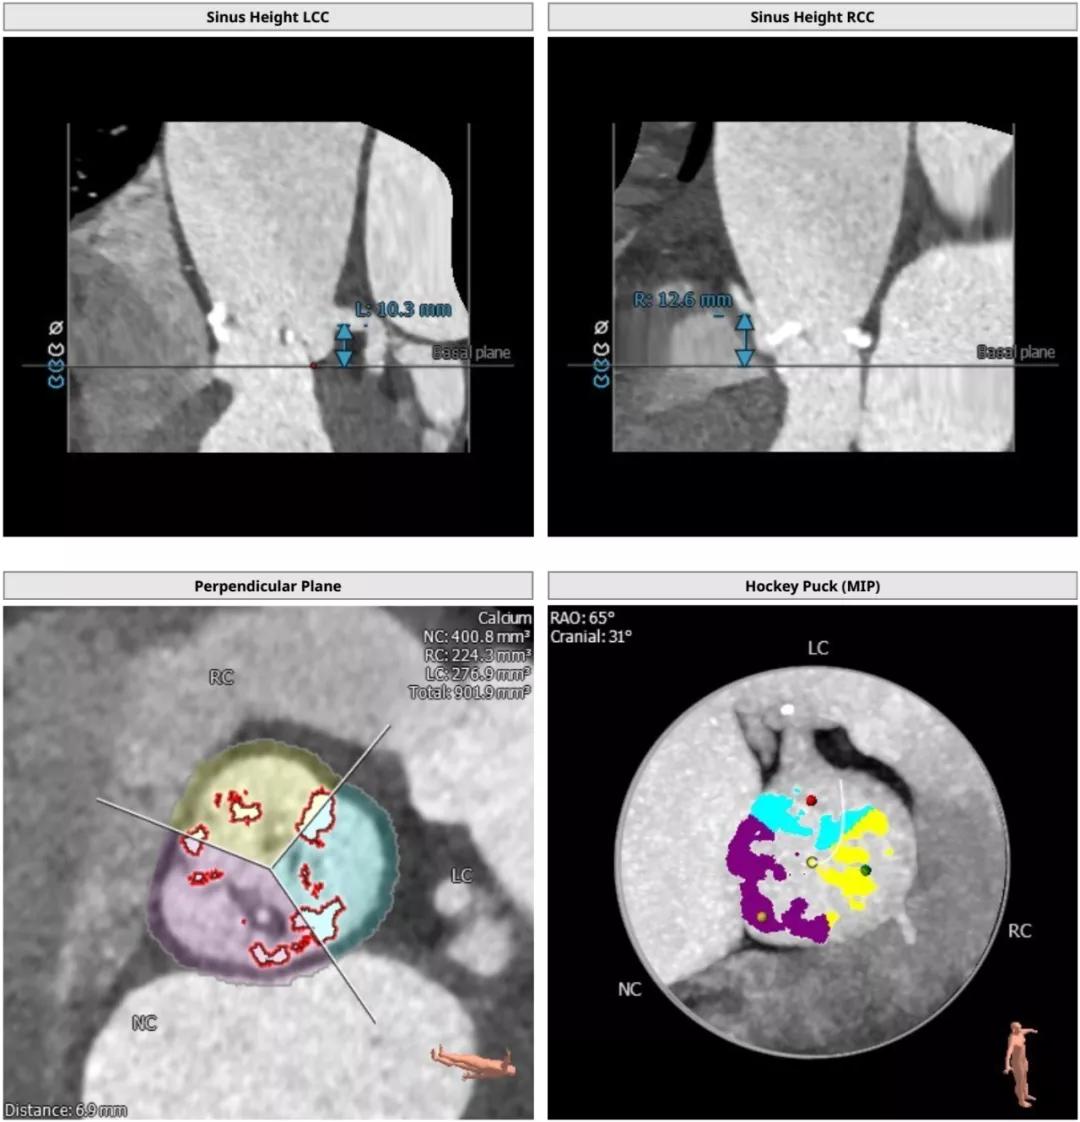

根部解刨:

手术过程